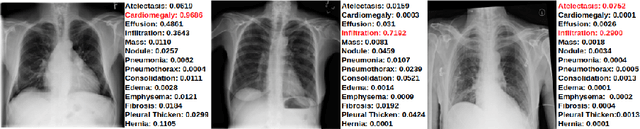

The training of deep learning models generally requires a large amount of annotated data for effective convergence and generalisation. However, obtaining high-quality annotations is a laboursome and expensive process due to the need of expert radiologists for the labelling task. The study of semi-supervised learning in medical image analysis is then of crucial importance given that it is much less expensive to obtain unlabelled images than to acquire images labelled by expert radiologists.Essentially, semi-supervised methods leverage large sets of unlabelled data to enable better training convergence and generalisation than if we use only the small set of labelled images.In this paper, we propose the Self-supervised Mean Teacher for Semi-supervised (S$^2$MTS$^2$) learning that combines self-supervised mean-teacher pre-training with semi-supervised fine-tuning. The main innovation of S$^2$MTS$^2$ is the self-supervised mean-teacher pre-training based on the joint contrastive learning, which uses an infinite number of pairs of positive query and key features to improve the mean-teacher representation. The model is then fine-tuned using the exponential moving average teacher framework trained with semi-supervised learning.We validate S$^2$MTS$^2$ on the thorax disease multi-label classification problem from the dataset Chest X-ray14, where we show that it outperforms the previous SOTA semi-supervised learning methods by a large margin.